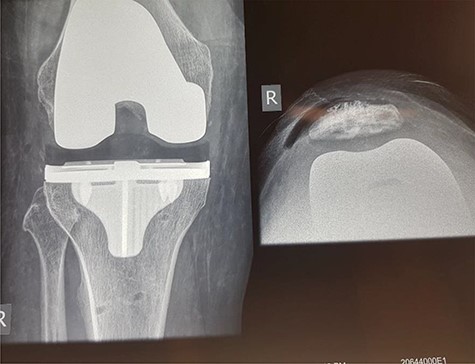

We report a case of a 72-year-old male with early lateral compartment osteoarthritis of the right knee, experiencing degenerative tear of the right meniscus. The patient had significant synovitis, medial compartmental pain and increasing weakness in the right knee. He presented with well-controlled hypertension and possible type 2 diabetes mellitus. The patient displayed no history of psychiatric disorders. They ceased taking a majority of supplements 2 weeks prior to surgery, continuing oral vitamin C (500 mg, twice daily) until 24 hours pre-surgery. The patient underwent a right triathlon/titanium total knee replacement with patella resurfacing (Fig. 1), utilizing Stryker precision navigation with a tourniquet release time of 8 minutes. Spinal anaesthetic with 20 μg/kg of fentanyl was used.

X-ray of patient’s knee following the total knee replacement with patella resurfacing.